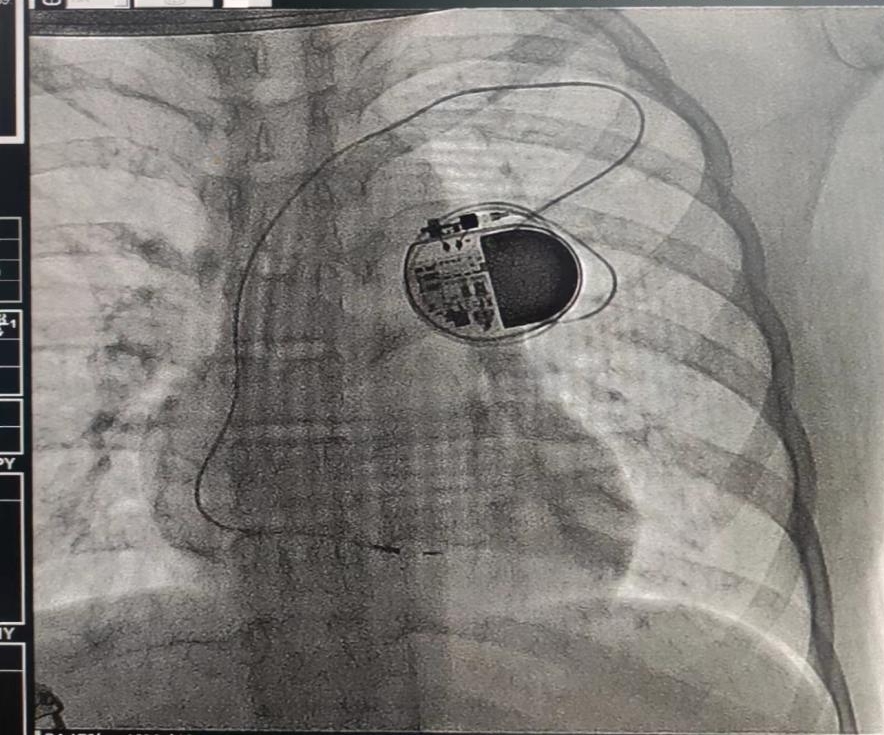

蓄上电,获“心”生,我院为12岁女孩再次成功植入心脏起搏器

小雨不到半岁时,就被诊断为先天性的三度房室传导阻滞。于是,满3岁那年,小雨在湖南省人民医院进行了人工心脏起搏器植入术。在起搏器的“罩”护下,小雨安全健康的成长着。今年713日,起搏器程控显示小雨的起搏器电池寿命不到1个月,必须尽快更换起搏器。考虑到小雨才12岁且需要终身起搏,需要多次更换、升级起搏器,接诊的张翼主任医师团队综合评估小雨初始植入时年龄、体重、原发疾病等因素及生长发育特点,制定个体化、精细化的起搏器更换方案并于718日为小雨行起搏器更换术。术后3天,小雨开心的出院了,新的起搏器将又为她续上新的征程。727日,小雨来院复查,各项指标均正常。